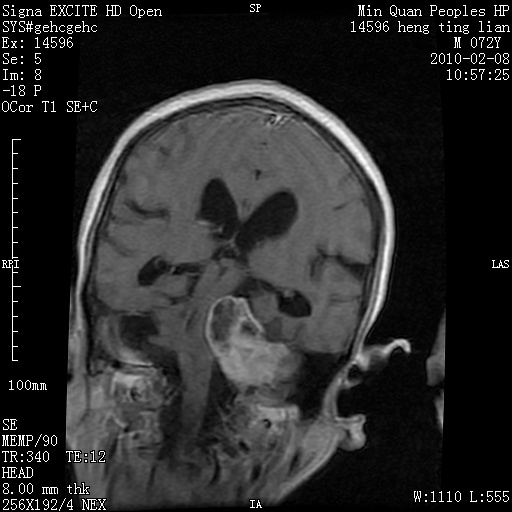

m,72,头疼,头晕两年,伴视力模糊三月,饮食呛咳两天。pe:颈部抵抗,左眼突出,左眼瞳孔约3mm,对光反射消失,双眼失明,伸舌困难,双肺呼吸音粗,心率110次/分,左上肢肌力i级,左下肢屈曲,肌张力高。现有08年2月19mri平扫及10年2月8日mri增强请会诊。ct病灶呈低密度伴散在点、片状等密度区,无明确钙化(无ct片资料可供上传)。[

脑外肿瘤,囊实性,环状不规则强化,内听道扩大,考虑神经源性肿瘤

左侧桥小脑区占位伴梗阻性脑积水----考虑 1神经鞘瘤 2室管膜瘤。

左侧桥小脑区神经鞘瘤伴梗阻性脑积水。

脑外肿瘤,病灶呈匍匐蔓延,表皮样囊肿可能性大。